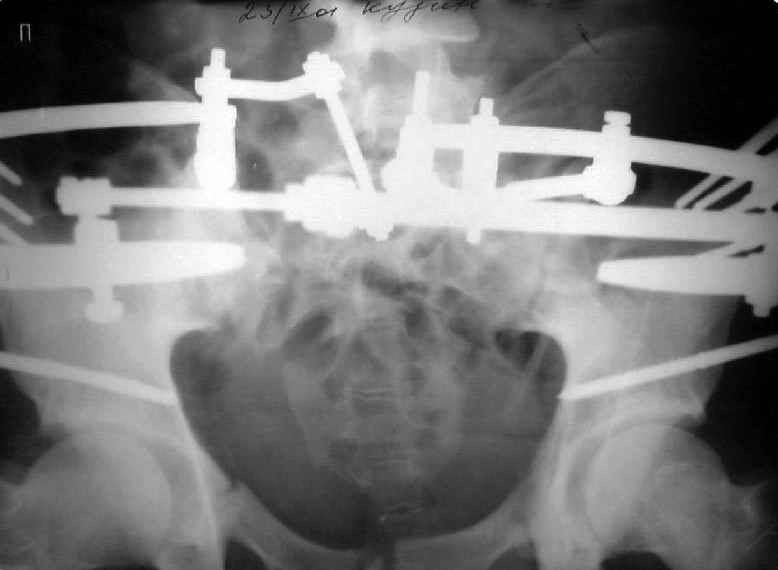

Уважаемые коллеги! Хотел-бы обсудить варианты лечения больной с застарелым переломом таза. Возраст 40 лет. Травма 11 месяцев назад. Главный травматолог Камчатского Военно-морского госпиталя Юрий Алексеевич Булахтин

Мы, как правило, в подобных случаях проводим оперативное лечение в несколько этапов. Первым устраняем деформацию при помощи АВФ (кольцевой конструкции с фиксацией задних отделов), вторым- выполняем введение илиосакралых винтов, накостный остеосинтез передних отделов.

Для информации к размышлению о возможности исправления имеющейся деформации предлагаю похожий случай.